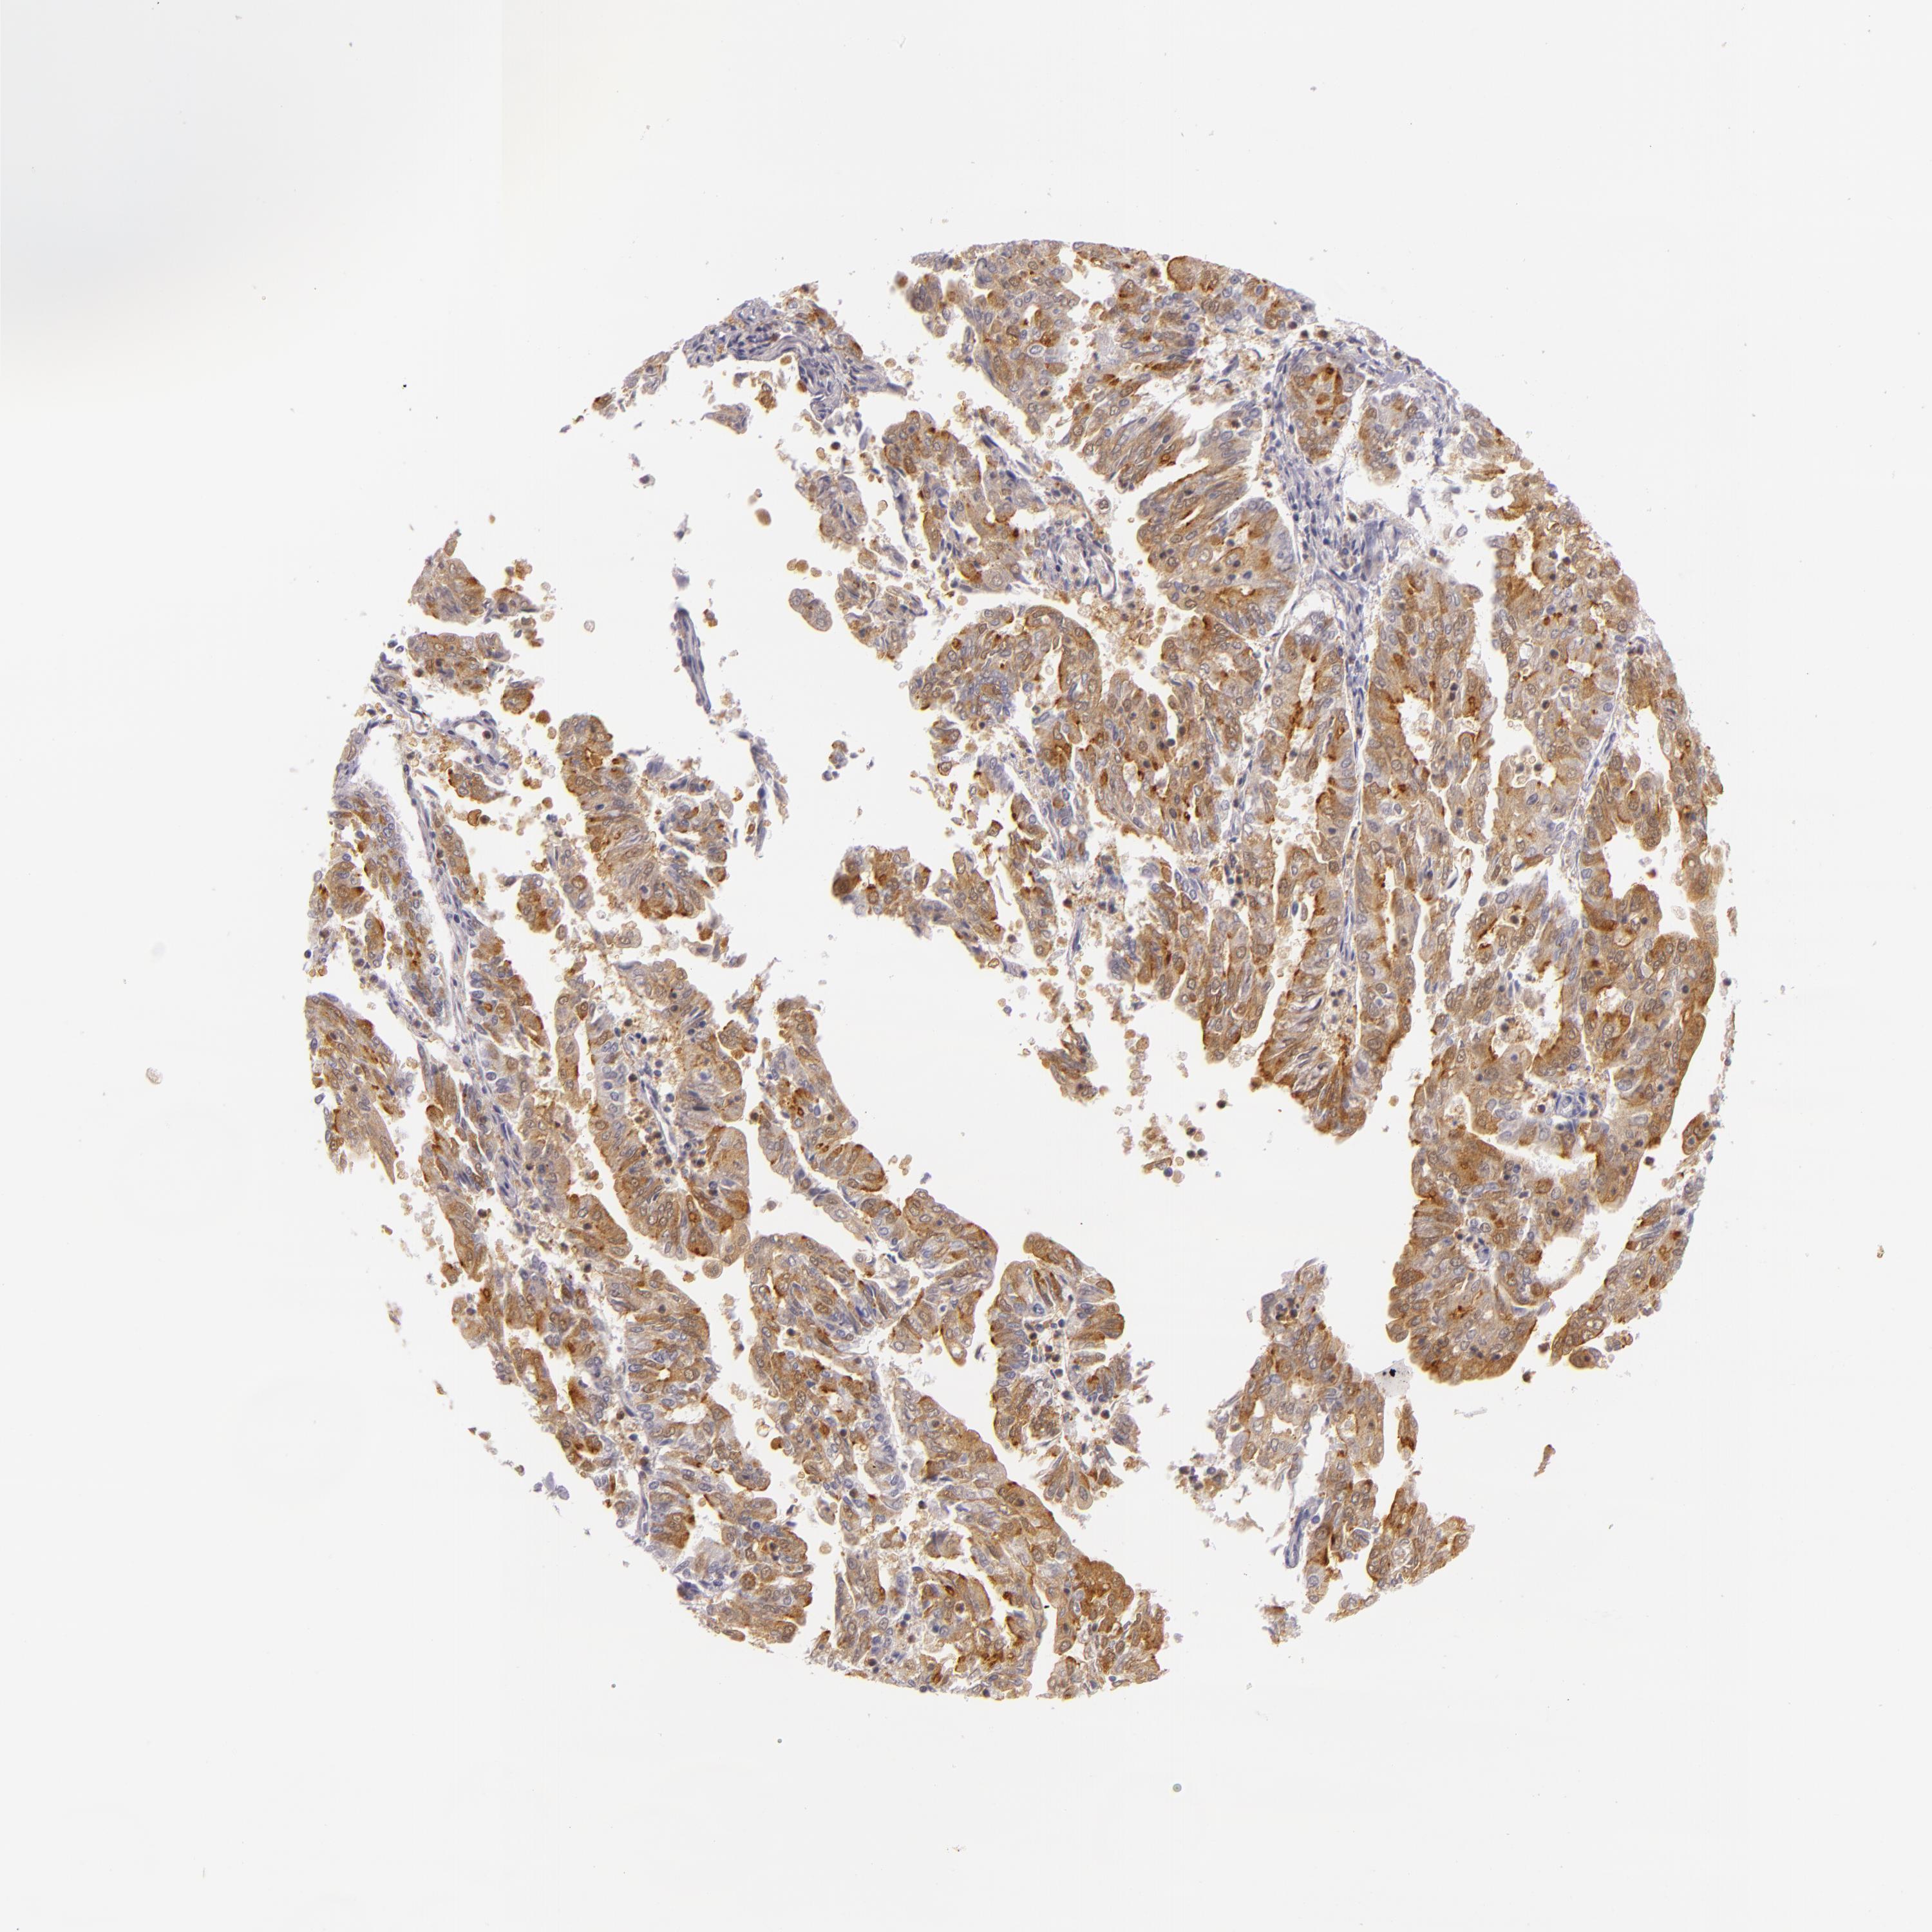

ENDOMETRIAL CANCER - Protein expressioni

A mouse-over function shows sample information and annotation data. Click on an image to view it in a full screen mode. Samples can be filtered based on level of antibody staining by selecting one or several of the following categories: high, medium, low and not detected. The assay and annotation is described here.

Note that samples used for immunohistochemistry by the Human Protein Atlas do not correspond to samples in the TCGA dataset.

Antibody stainingi

Antibody staining in the annotated cell types in the current human tissue is reported as not detected, low, medium, or high, based on conventional immunohistochemistry profiling in selected tissues. This score is based on the combination of the staining intensity and fraction of stained cells.

Each image is clickable and will lead to virtual microscopy that enables deeper exploration of all samples and also displays staining intensity scores, fraction scores and subcellular localization as well as patient and tissue information for each sample.

Antibody HPA001749

Staining

High

Medium

Low

Not detected

Intensity

Strong

Moderate

Weak

Negative

Quantity

>75%

75%-25%

<25%

None

Location

Nuclear

Cytoplasmic/membranous

Cytoplasmic/membranous,nuclear

Adenocarcinoma, NOS